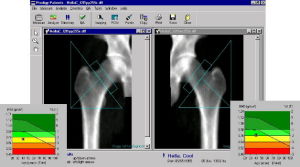

原發性骨質疏鬆症近30年來對骨量的測定技術有很大進展,常用的骨密度(BMD,為骨礦鹽量/骨面積)測量方法有:單光子吸收法(SPA)、雙光子吸收法(DPA)、雙能X線吸收法(DEXA)和定量計算機控制X線掃描法(QCT)等。骨密度測量有利於了解早期骨量減少,預測骨折發生的可能性和監測給予防治藥物或措施,測量任何部位的骨密度,對身體各部位骨折都是一項有效的預測指標。DEXA測近端股骨骨密度對預測髖部骨折危險性優於其他部位的測量。

2、有條件的套用雙能X線骨密度儀;根據測量結果和上述標準判斷是否患有骨質疏鬆症及嚴重的程度。

骨質疏鬆症的診斷標準(WHO,白人婦女):正常為骨密度(BMD)或骨礦含量(BMC)在正常青年人平均值的1個標準差(1SDT-積分,即T-score)之內;低骨量或骨量減少為BMD或BMC低於正常青年人平均值的1~2.5SD之間;骨質疏鬆症為BMD或BMC低於正常青年人平均值的2.5SD;嚴重骨質疏鬆症為BMD或BMC低於正常青年人平均值的2.5,伴有1個或1個以上部位骨折。如BMD值與同性別、同年齡健康者平均值相比,〈1SD即為Z-積分(Z-score),將在以後一年中骨折危險性增加2倍,Z-積分為-2.5者骨折危險性將增加4倍。